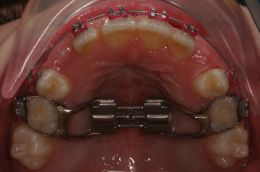

Come è possibile vedere dalle immagini la paziente si trovava in dentizione mista tardiva, con cross-bite bilaterale ma con i 5-ti decidui in ottime condizioni.

Si decide di utilizzare un espansore rapido del palato bondato sui denti da latte (REP on five).